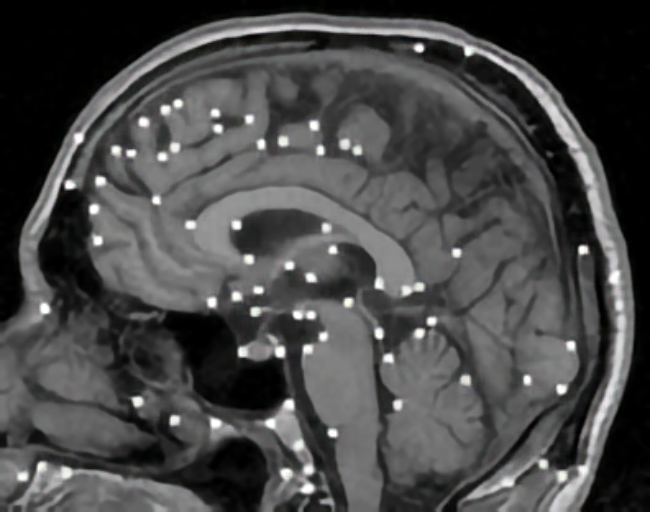

Elastic registration of 2D and 3D multimodal medical images (MR, CT) for diagnosis, surgical planning, and therapy. Spline-based registration approaches using landmarks, intensity information, and landmark localization uncertainties.

Localization of 3D anatomical point landmarks in 3D tomographic images. Development of differential and model-based approaches.

Brain shift correction for intraoperative navigation based on elastic registration algorithms.